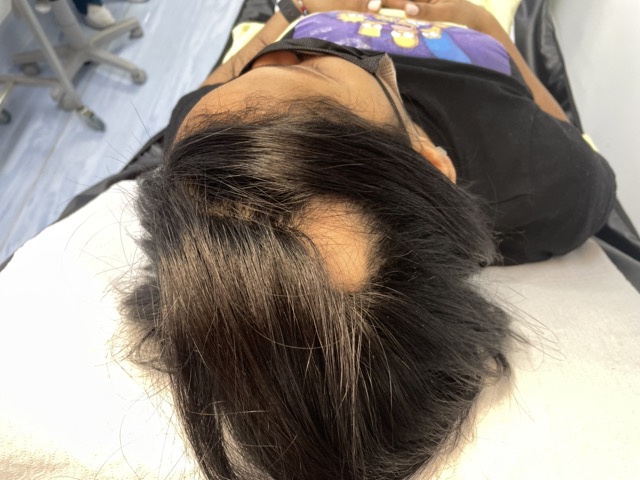

- Examen físico del cuero cabelludo con técnicas avanzadas de observación.

- Tricoscopía/capilografía y exámenes complementarios, si es necesario, para identificar el tipo de alopecia.

Utiliza luz LED de espectro específico para estimular el metabolismo celular, reducir la inflamación y favorecer el crecimiento de cabello más fuerte y saludable. - Tricoscopía. Examen médico no invasivo que permite observar en detalle el cuero cabelludo y los folículos pilosos mediante un dermatoscopio digital.

IMÁGENES EXAMEN CAPILAR